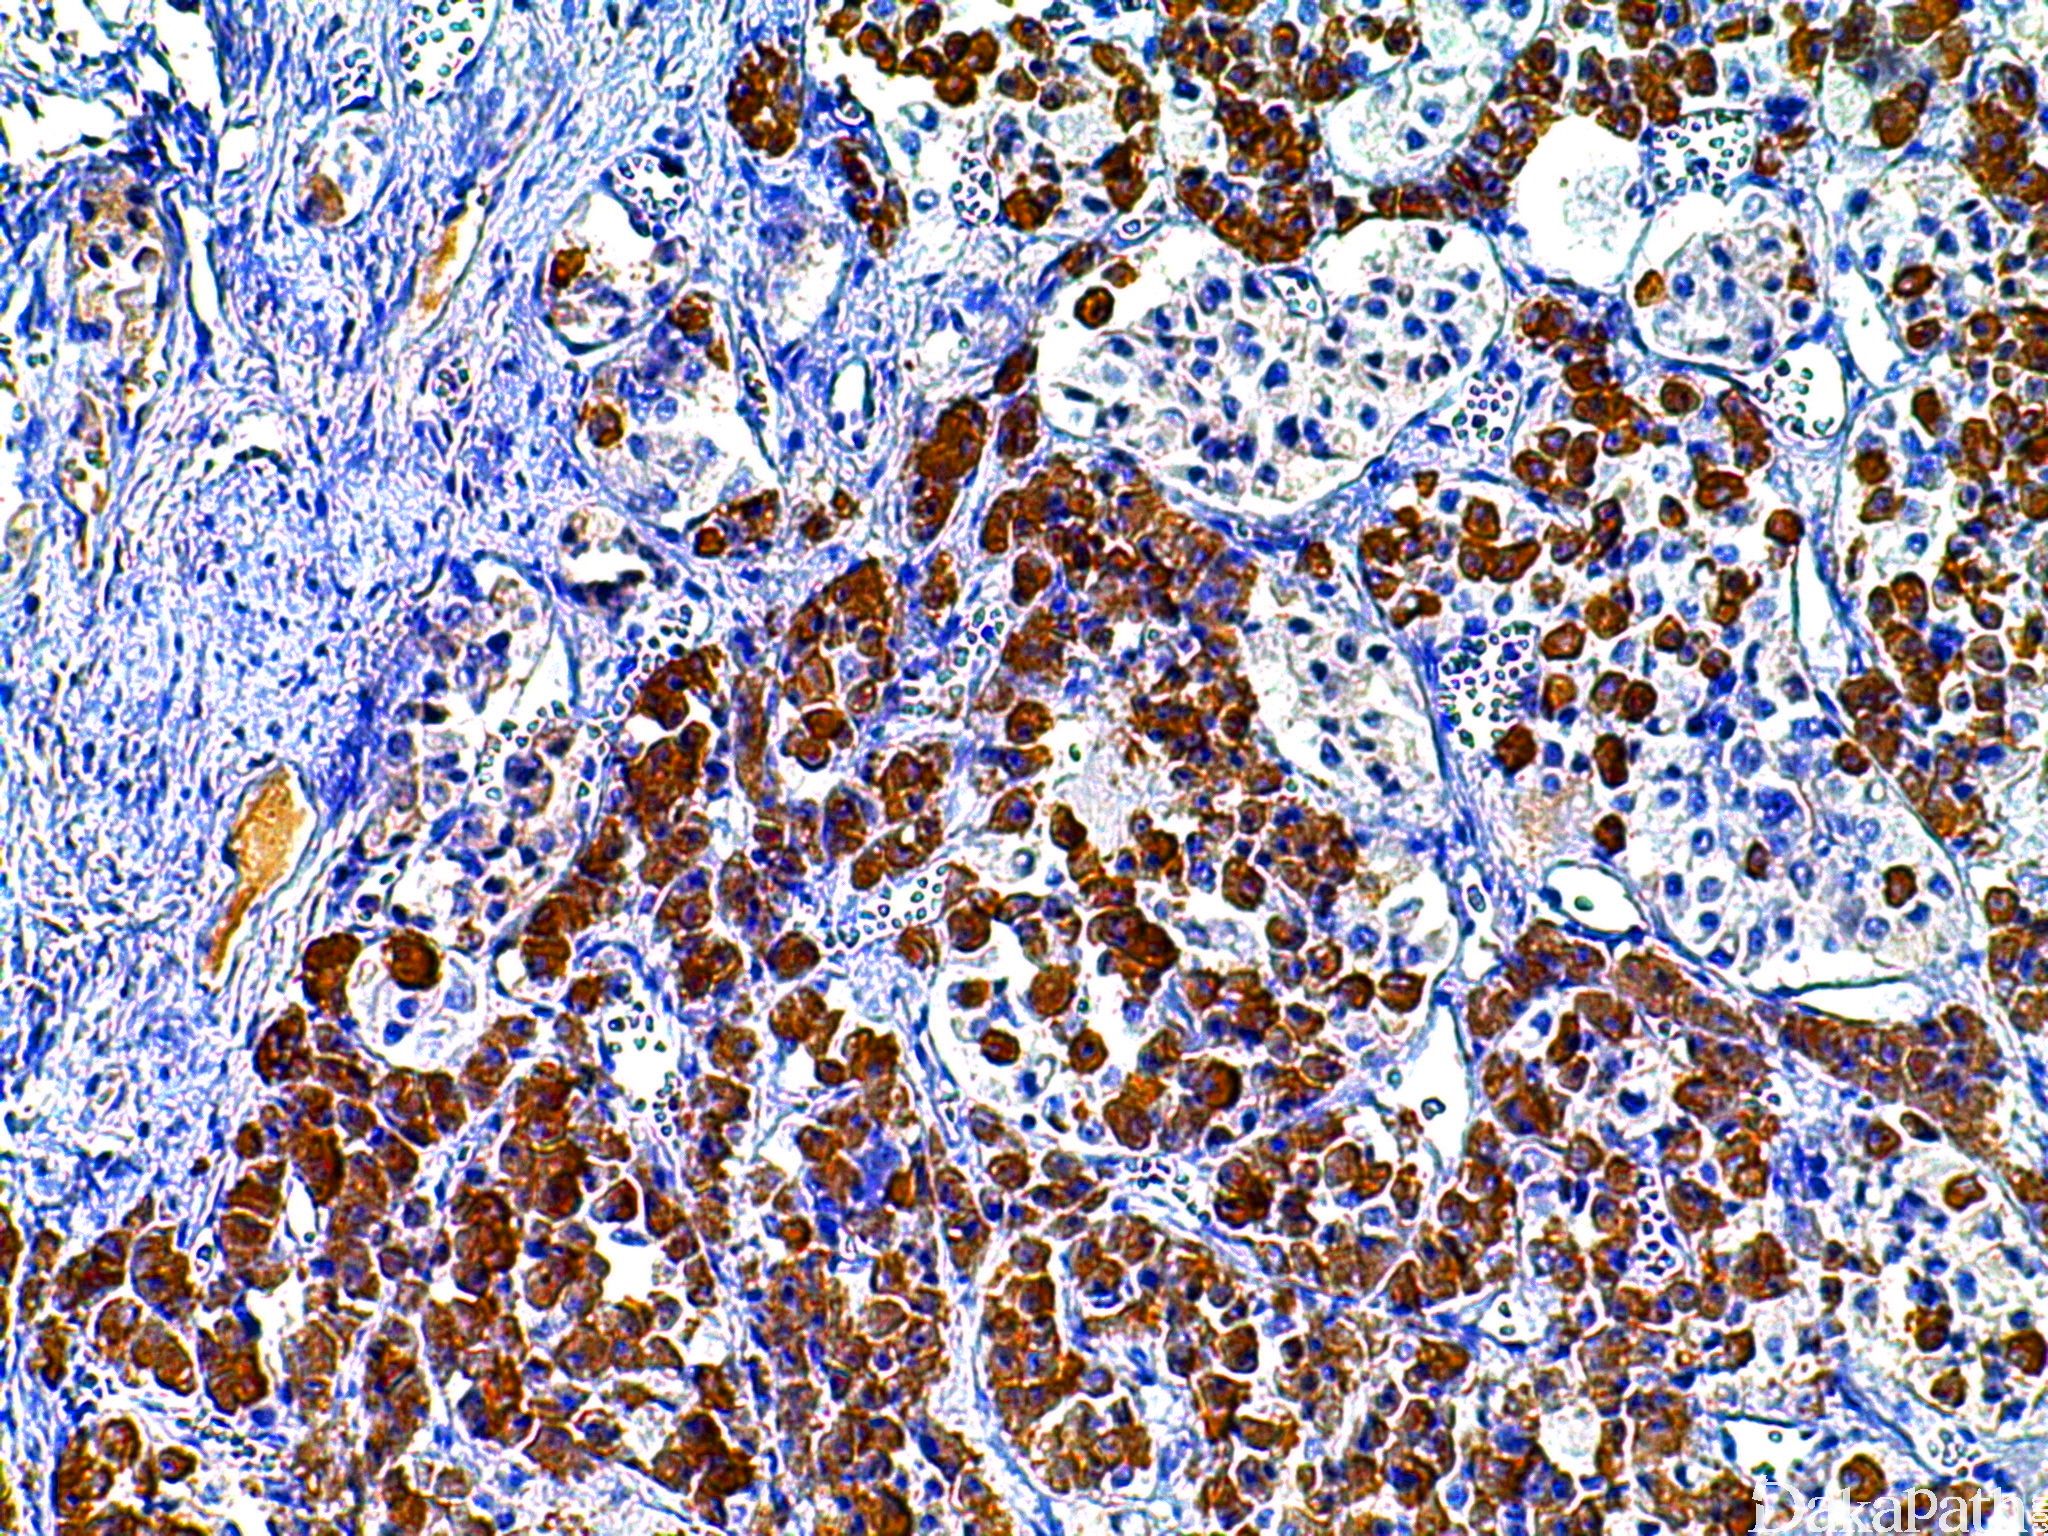

几乎全部阳性(≥95%的病例阳性): 垂体腺瘤,分泌生长激素、肺硬化性肺细胞瘤,多角形细胞

经常阳性(<75%,≥55%的病例阳性): 肺硬化性肺细胞瘤

几乎全部阴性(<5%的病例阳性): 结直肠腺癌、间皮瘤,NOS、肺鳞状细胞癌、垂体腺瘤,裸细胞、脑垂体梭形细胞嗜酸细胞瘤、肺腺鳞癌、大细胞神经内分泌癌、肺硬化性肺细胞瘤,立方细胞、肺腺癌